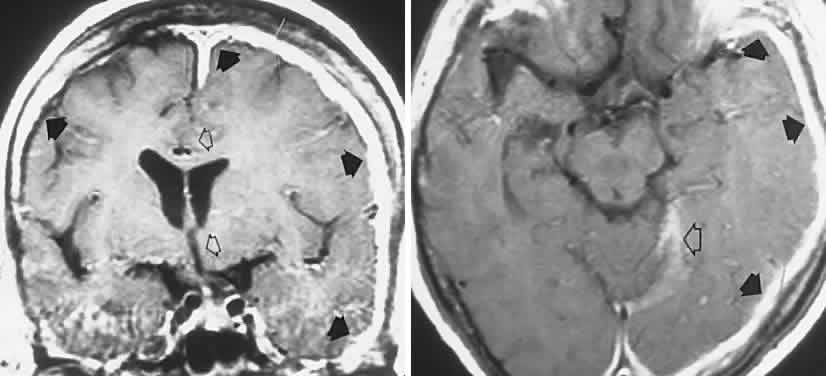

Unclassified

In addition to retinal changes, pallor of the optic disc occurs in numerous storage disorders, the nerve being affected by several mechanisms. Optic atrophy occurs when abnormal glycolipids are stored in retinal ganglion cells with subsequent neuronal death and nerve pallor, such as occurs in Tay-Sachs disease (Gm2 gangliosidosis), but ophthalmoscopic evidence of optic atrophy is not invariable. Tay-Sachs is an autosomal recessive inherited disease, resulting from mutations of the hexosaminidase (Hex) A gene coding for the alpha-subunit of beta-D-N-acetyl-hexosaminodase. Juvenile and adult Hex A deficiencies are rare, less severe variants. Both infantile and late forms are most prevalent among Ashkenazi (roughly, Middle and Eastern European) Jews, but are reported in non-Jews, in whom clinically benign mutations may occur.28,29 MRI findings include hyperintensities in basal ganglia and thalamus, with marked brain atrophy and diffuse white matter lesions; these findings likely reflect accumulation of Gm2 ganglioside.30 Similarly, in Gm1 gangliosidosis (generalized gangliosidosis; “Tay Sachs disease with visceral involvement”), there is also an abnormal deposition of ganglioside in the retina, with subsequent atrophy of the nerve, but it is a mucopolysaccharide that accumulates in the viscera.